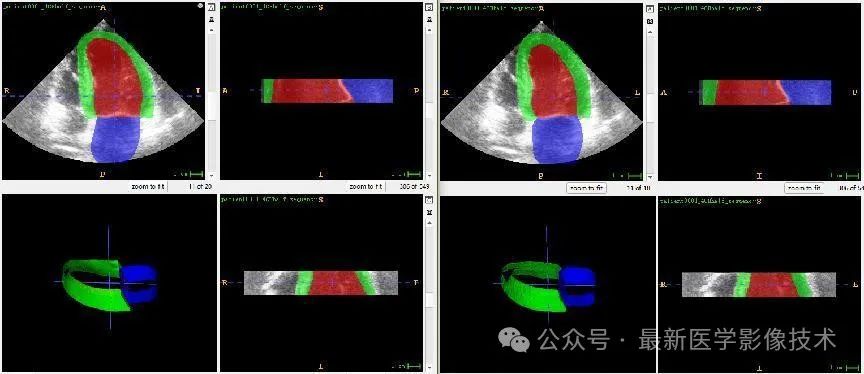

4、验证集部分分割结果

左边是金标准结果,右边是预测结果。